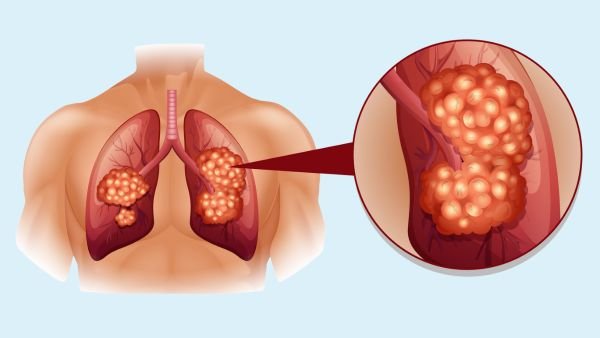

Lung cancer